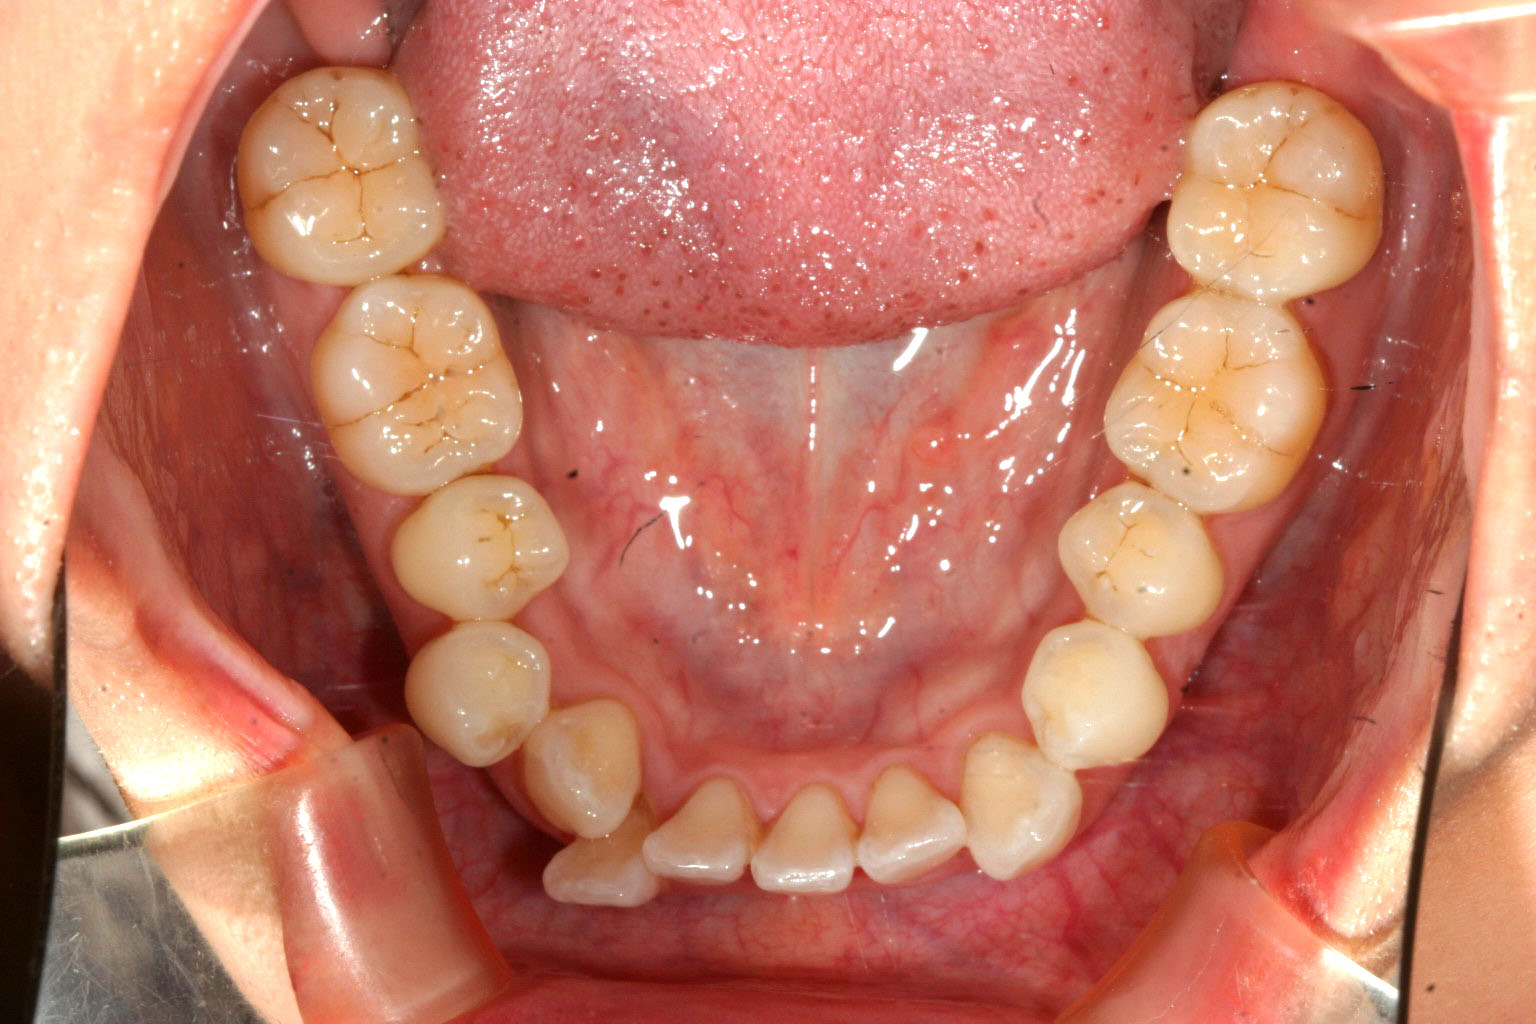

下顎のアーチが狭い為に叢生が目立ちます。

下顎のアーチも広げ叢生も改善しています。